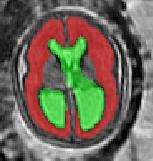

Limiting failures of machine learning systems is of paramount importance for safety-critical applications. In order to improve the robustness of machine learning systems, Distributionally Robust Optimization (DRO) has been proposed as a generalization of Empirical Risk Minimization (ERM). However, its use in deep learning has been severely restricted due to the relative inefficiency of the optimizers available for DRO in comparison to the wide-spread variants of Stochastic Gradient Descent (SGD) optimizers for ERM. We propose SGD with hardness weighted sampling, a principled and efficient optimization method for DRO in machine learning that is particularly suited in the context of deep learning. Similar to a hard example mining strategy in practice, the proposed algorithm is straightforward to implement and computationally as efficient as SGD-based optimizers used for deep learning, requiring minimal overhead computation. In contrast to typical ad hoc hard mining approaches, we prove the convergence of our DRO algorithm for over-parameterized deep learning networks with ReLU activation and a finite number of layers and parameters. Our experiments on fetal brain 3D MRI segmentation and brain tumor segmentation in MRI demonstrate the feasibility and the usefulness of our approach. Using our hardness weighted sampling for training a state-of-the-art deep learning pipeline leads to improved robustness to anatomical variabilities in automatic fetal brain 3D MRI segmentation using deep learning and to improved robustness to the image protocol variations in brain tumor segmentation. Our code is available at https://github.com/LucasFidon/HardnessWeightedSampler.